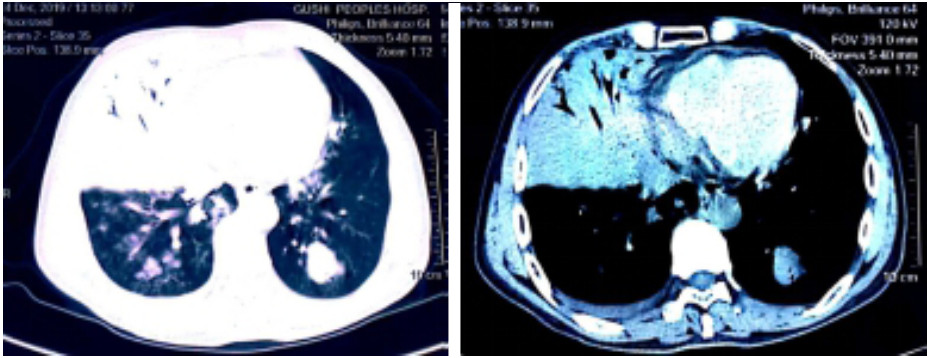

患者,男,54岁。因“咳嗽咳痰伴发热12 d”于2019年12月14日收入院。12 d前受凉后出现咳嗽,咳少量痰,发热,在天津某诊所拟“感冒”治疗后,症状无好转。7 d前至宁波某医院门诊治疗,症状未见改善。2 d前咳嗽咳痰加重,大量灰褐色痰,有腥臭味,并出现呼吸急促及高热(最高39.0 ℃)。1 d前在河南某医院胸部CT示右肺上叶及中叶大片实变影,左肺上下叶可见散在团块状密度增高影(图 1),住院1 d后出院,于12月14日晚收入我院。上述治疗用药患方均未能提供。患者10年前因胃溃疡行胃部分切除术,无吸烟酗酒病史,无牙周病病史。患者为建筑工人,平日常辗转各建筑工地工作。体格检查:体温39.3 ℃,心率155次/min,呼吸35次/min,血压131/81 mmHg(1 mmHg=0.133 kPa),吸氧3 L/min时经皮氧饱和度90%,双肺呼吸音粗,可闻及粗湿性啰音。入科后实验室检查:白细胞5.03×109/L,中性粒细胞百分比0.97,淋巴细胞百分比0.04,血红蛋白124 g/L,血小板137×109/L;C反应蛋白122.5 mg/L,降钙素原42.42 ng/mL,白介素-6 > 5 000 pg/mL;生化:白蛋白16.7 g/L,谷草转氨酶159 U/L,血肌酐208 μmol/L,尿素氮25.07 mmol/L,乳酸2.52 mmol/L。血浆D-二聚体3 630 μg/L,肌红蛋白 > 4 057 ng/mL,肌酸激酶1 471 U/L。空腹血糖8.4 mmol/L,糖化血红蛋白6.2%,人类免疫缺陷病毒抗体、甲型及乙型流感病毒抗体、痰抗酸染色均阴性。G试验 < 10 pg/mL,GM试验0.3 pg/mL,癌胚抗原1.66 ng/mL,甲胎蛋白0.7 ng/mL,T细胞亚群:总T淋巴细胞计数106/μL,CD4+T 54/μL,CD8+T 40/μL。

图 1 患者2019年12月14日胸部CT结果(右肺上叶及中叶大片实变影,左肺上下叶可见散在团块状密度增高影)